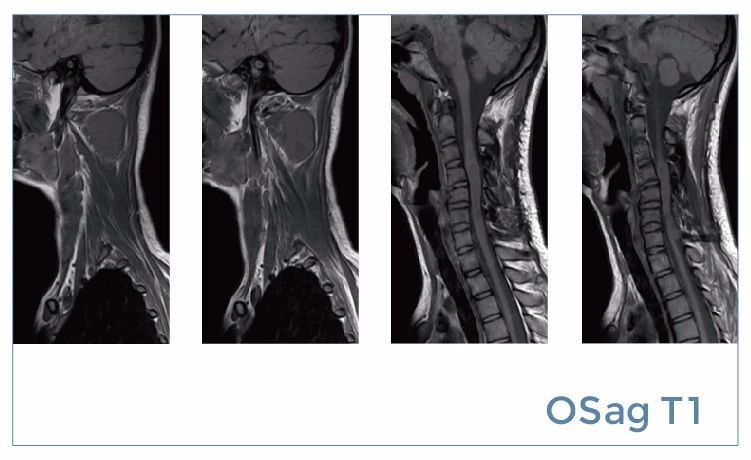

【朗润影像档案】磁共振影像病例分享(编号20190816)